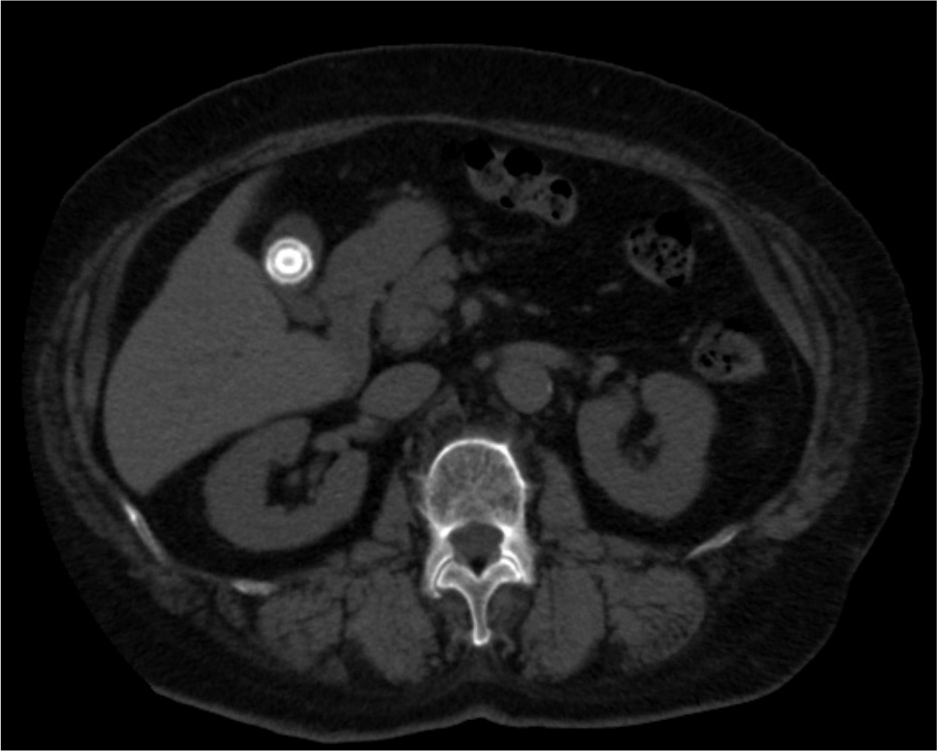

消化酵素を溜めている袋(胆のう)の中に何らかの原因でできた石を胆石と呼び、胆嚢の中に石があることを胆のう結石といいます。検診などで見つかることも多く、無症状の場合には経過を観察することもありますが、石が胆管に詰まると胆のう結石症を発症します。その症状は、みぞおちの右側を中心とした激しい痛みが典型的で、右肩や背中の痛みを伴う場合もあります。血液検査や腹部CT検査などで診断し治療方針を決めていきます。